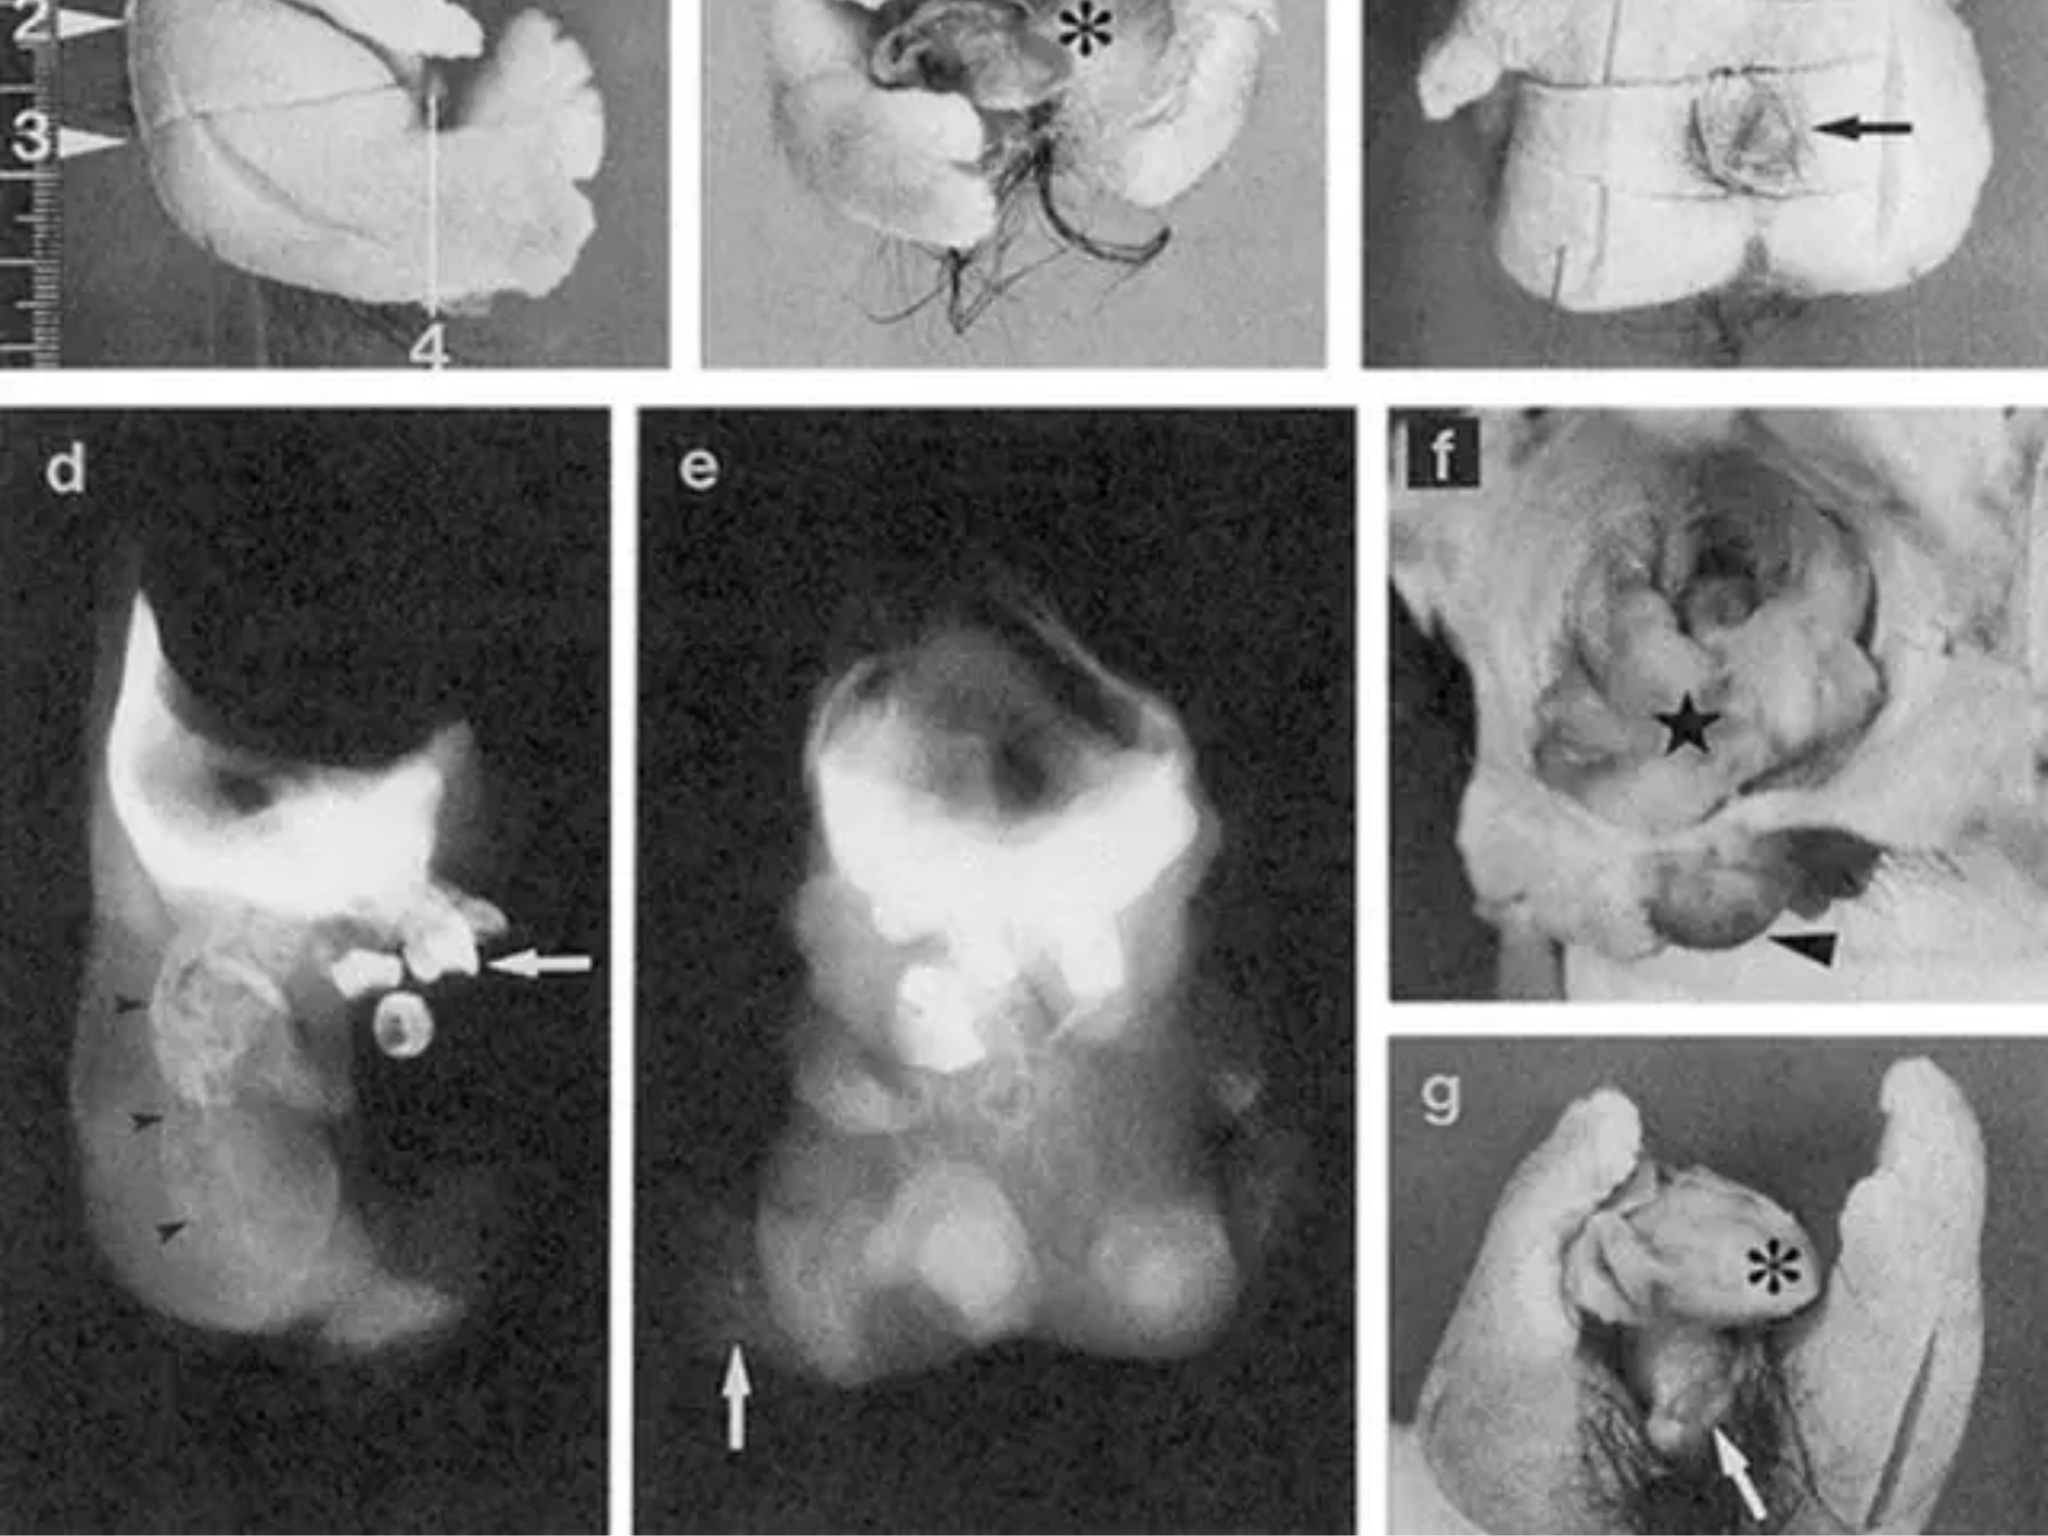

Brzmi jak scena z filmu grozy, ale to rzadki i opisany w literaturze medycznej przypadek. Podczas operacji guza jajnika u 25-letniej pacjentki w Japonii lekarze natrafili na niezwykle nietypową postać potworniaka: wewnątrz znajdowała się zorganizowana struktura z „głową, tułowiem i kończynami” – na tyle przypominająca miniaturową postać, że w publikacjach popularnonaukowych zaczęto o niej pisać jak o „lalkowym ciele”.